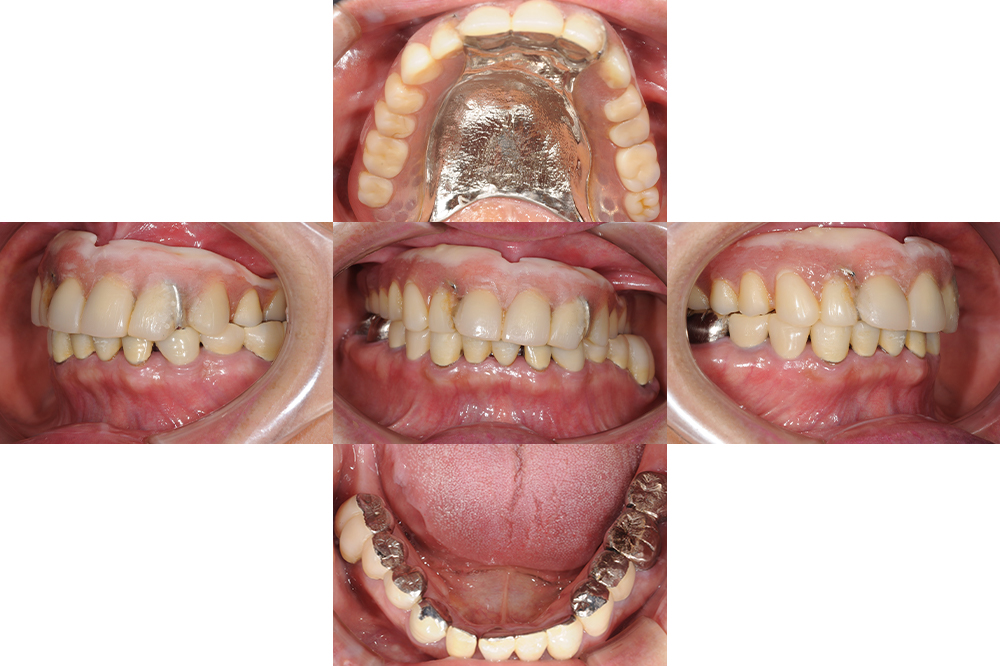

年齢 67歳 性別 女性 主訴/ニーズ 前歯がグラグラする 治療期間 1年 治療内容 ・インプラント ・セラミック修復 ・金属床義歯 費用 300万円 治療経過 上顎の残存歯が残念ながら虫歯で抜歯を余儀なくされ総義歯となった。 上顎の固定式も検討したがインプラントの…